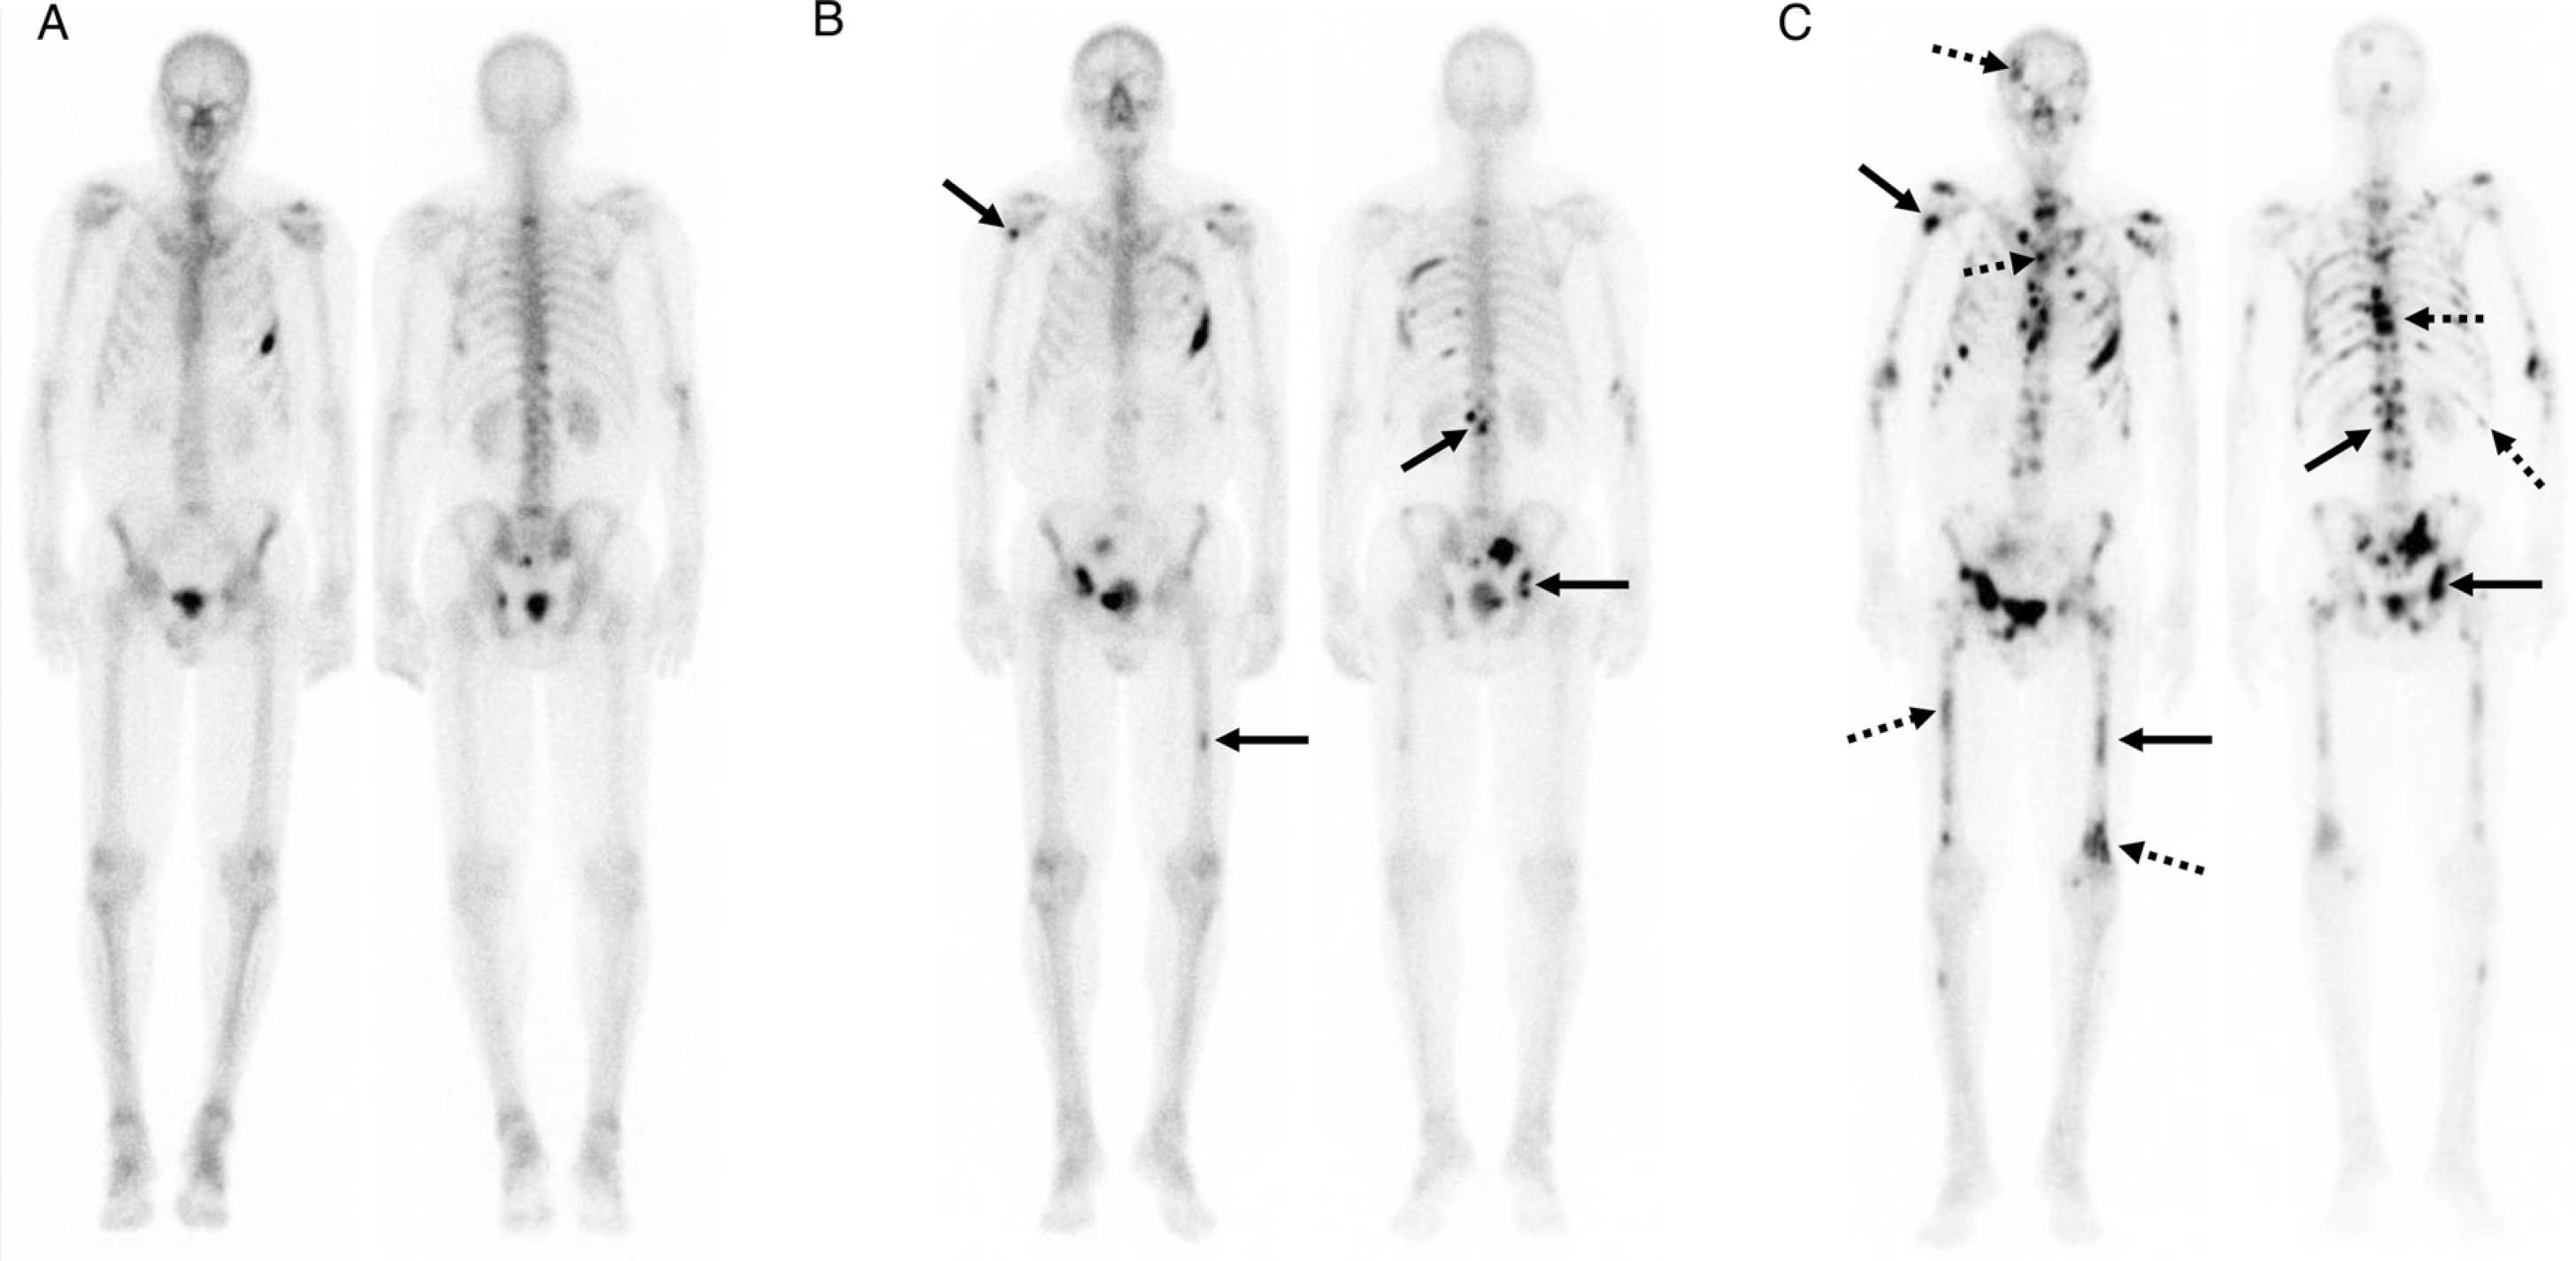

Imaging response assessment for oncology: An algorithmic approach

June 07, 2022. Author(s): Kathleen Ruchalski, Rohit Dewan, Victor Sai, Lacey J. McIntosh, Marta Braschi-Amirfarzan. Source: European journal of radiology open